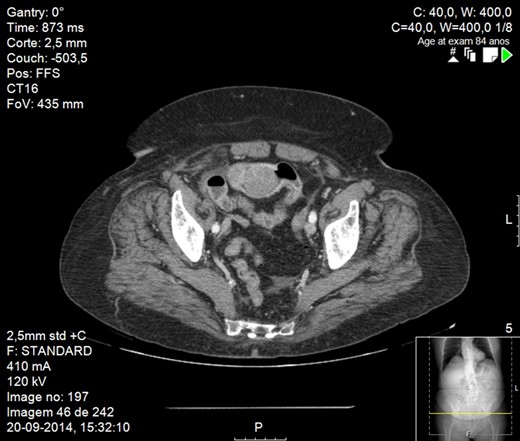

Abdominal X-ray revealed small bowel distension with multiple hydroaeric levels. Abdominal computed tomography (CT) scan (Figs 1 and 2) demonstrated distension of the small bowel due to an intraluminal mural mass with 4 cm in diameter, being the intestine collapsed distal to it. There was no evidence of other metastatic disease, including the liver.

CT scan image showing small bowel obstruction due to polypoid intraluminal masses.